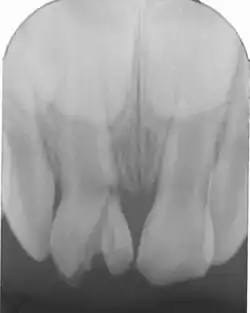

Fracture coronaire amélo-dentinaire sans exposition pulpaire

Fracture coronaire amélo-dentinaire sans exposition pulpaire : c'est une perte de substance coronaire avec douleur plus ou moins provoquée par le froid. Le traitement consiste à protéger le complexe pulpo-dentinaire, suivi d'une reconstitution coronaire.